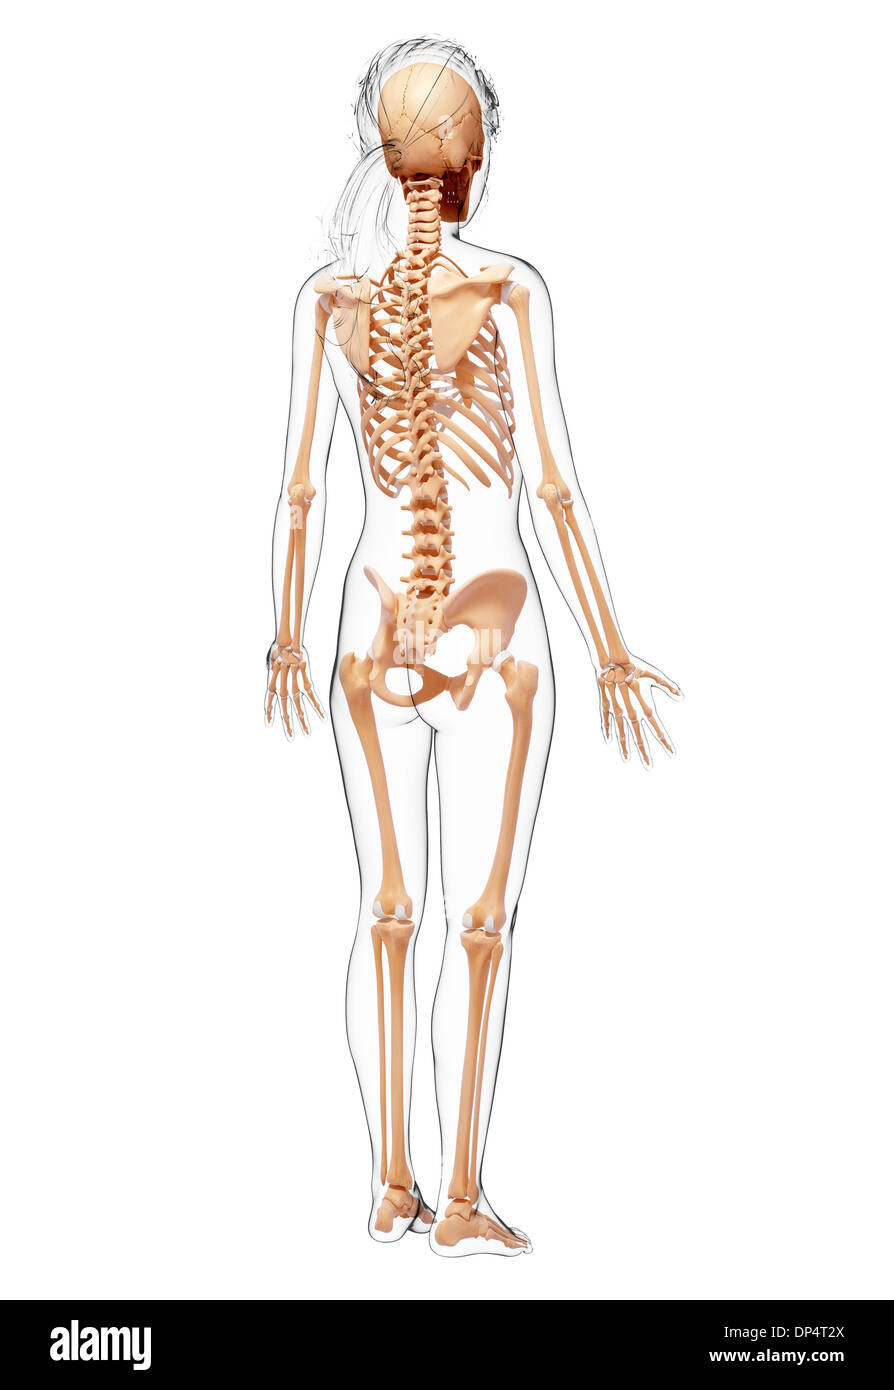

, Artwork Banque D'Imageshttps://www.alamyimages.fr/image-license-details/?v=1https://www.alamyimages.fr/artwork-image65260242.html

, Artwork Banque D'Imageshttps://www.alamyimages.fr/image-license-details/?v=1https://www.alamyimages.fr/artwork-image65260242.htmlRFDP4T2X–, Artwork